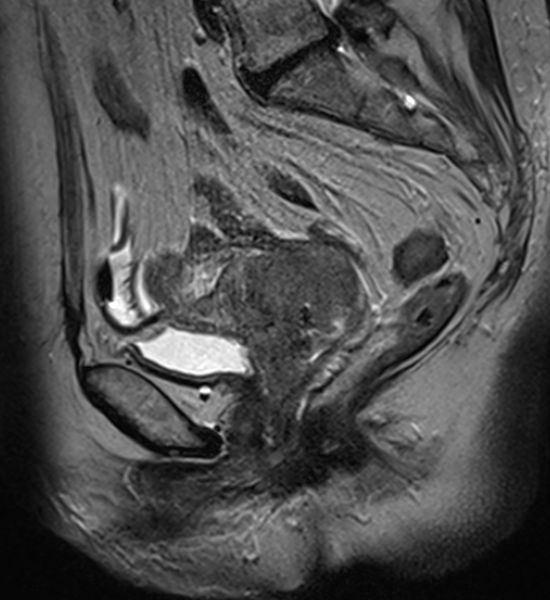

| MRT | 71jährige Frau, die wegen Uterus-Totalprolaps eingeliefert wurde. Der Uterus wurde reponiert und zeigte einen 5cm großen Zervixtumor. | |||